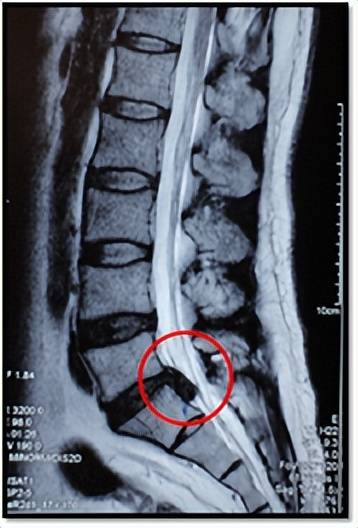

这是1例髓核游离脱出的病人,若是随便乱推拿,很有可能会压迫到脊髓及神经根加重原有的症状,甚至引起瘫痪。

因此,若已确诊为腰椎间盘突出症,又不能确定是否适合推拿,一定要咨询医生,并且找专业的康复科或骨科医生进行推拿治疗。